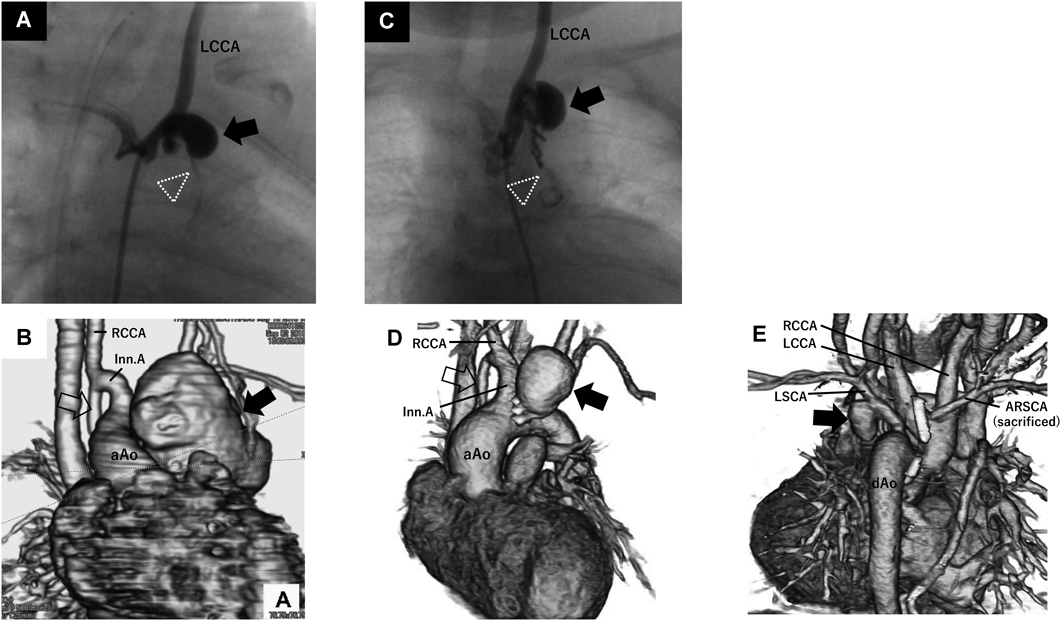

Fig. 1 Angiographic and three-dimensional computed tomographic images of pseudoaneurysm

A) Angiographic image in case 2. Modified Blalock–Taussig shunt (mBTS) was almost completely obstructed (dotted arrowhead) and pseudoaneurysm (solid arrow) was formed at the proximal anastomotic site of the mBTS. B) Three-dimensional computed tomographic (3DCT) image 23 days after angiography in case 2. Pseudoaneurysm was markedly expanded (solid arrow). Right original BTS was represented (open arrow). C) Angiographic image in in case 3. Note almost completely obstructive mBTS (dotted arrowhead) and pseudoaneurysm (solid arrow) at the proximal anastomotic site of the mBTS, similar to case 2. D) 3DCT image 8 days after angiography in case 3. Note expanded pseudoaneurysm (solid arrow) and right original BTS (open arrow), also similar to case 2. E) 3DCT image in case 6. Pseudoaneurysm (solid arrow) was formed at the proximal anastomotic site of the mBTS. aAo, ascending aorta; ARSCA, aberrant right subclavian artery; dAo, descending aorta; Inn. A, innominate artery; LCCA, left common carotid artery; LSCA, left subclavian artery; RCCA, right common carotid artery

症例2, 3, 6でmBTS近位側吻合部の仮性瘤を認めた(Fig. 1).感染性mBTS閉塞に伴うmBTS近位側吻合部の感染性仮性瘤はこれまでも報告されており1–7),感染の関与を示唆する重要な所見となる.